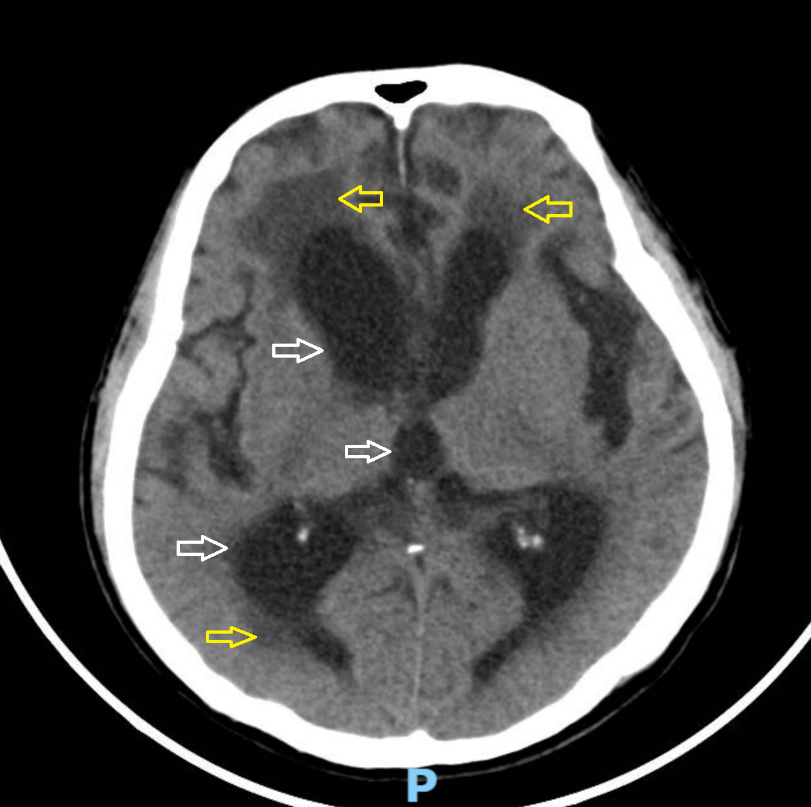

Hình ảnh cắt lớp vi tính của bệnh não úng thủy với dấu hiệu giãn não thất trung bình (mũi tên trắng), ứ dịch não tủy (mũi tên vàng). Ảnh: BVCC

Tại khoa Cấp cứu của bệnh viện, người bệnh được thăm khám và chỉ định chụp cắt lớp vi tính (CT Scan) sọ não. Hình ảnh CT Scan tại đây cho thấy não thất giãn lớn, có hình ảnh ứ dịch não tủy trong các não thất.

Sau khi hội chẩn, bác sĩ chuyên khoa Ngoại thần kinh đã nhận định ngay đây có thể là tình trạng não úng thủy - một tình trạng bệnh lý hay gặp trên những người bệnh cao tuổi.